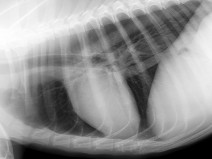

• Journée TP Radiographie du Thorax

Etant donné le succès de notre première journée consacrée à la radiographie thoracique, il y a 4 ans maintenant, nous avons à nouveau invité Delphine Rault et Anais Combes pour traiter ce sujet.

Au programme de la journée, présentations théoriques et lecture de radiographies normales et pathologiques sur les six stations de travail de l'AFVAC.

Deux niveaux de compétences vous se...